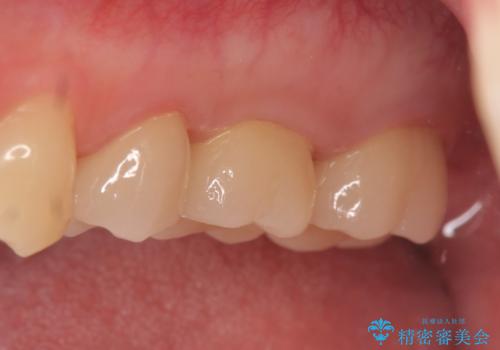

オールセラミッククラウンについて

今回用いたオールセラミッククラウンはジルコニアフレームという白い素材の上にセラミックを盛っているため、審美性が非常に高いのが特徴です。

また、ジルコニアは人工ダイヤモンドの材料にも使われているほど高い強度を持っており、そのためオールセラミッククラウンは審美性だけでなく、奥歯やブリッジの補綴も可能とするクラウンです。